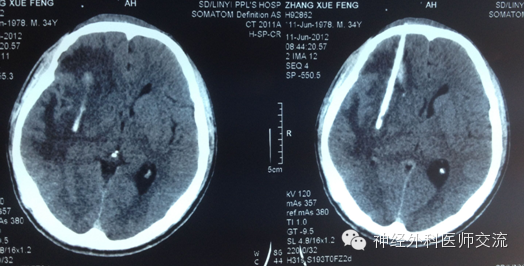

再来个延迟手术病例,这个病人开始不需要做,但是年轻人,反应重

一、 壳核出血

壳核出血占高血压脑出血的50%以上,积极完善地救治壳核出血对于降低脑出血的病死率,提高患者的生活质量具有重要意义。

③ 延期(>3 d):不主张延期手术,但是受到患者入院时间和病人或家属对该项技术的理解信任程度的限制。此期行介入手术治疗仍具有现实意义。